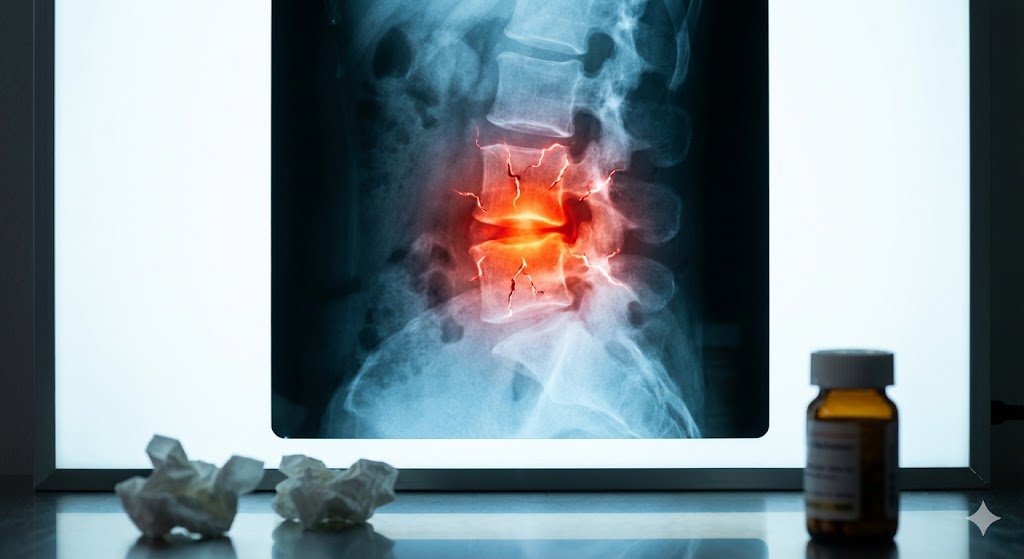

Hérnia de disco pode curar sozinha? A verdade científica que poucos sabem

Descubra quando é possível evitar a cirurgia e quando ela se torna necessária. Sim — muitas hérnias de disco podem melhorar sem cirurgia. Estudos mostram que até 70% dos casos têm regressão parcial ou total com tratamento conservador. Mas isso depende do tipo de hérnia, dos sintomas e da evolução clínica. A regressão acontece porque […]

Protrusão, extrusão e sequestro: as diferenças que ninguém te explicou sobre a hérnia de disco

Saiba qual tipo de hérnia você tem e por que isso muda totalmente o tratamento. Nem todas as hérnias de disco são iguais. Dentro dos laudos e exames de ressonância, termos como “protusão”, “extrusão” e “sequestro discal” podem confundir e assustar o paciente — mas cada um deles significa um grau diferente de deslocamento do […]

Hérnia de Disco: o que é, por que dói e como tratar

Entenda de forma simples o problema de coluna que mais causa dor e incapacidade no mundo. A hérnia de disco ocorre quando uma parte do disco intervertebral — uma espécie de “amortecedor” entre as vértebras — se desloca e começa a comprimir os nervos. Essa compressão gera dor intensa, formigamento, perda de força e, em […]